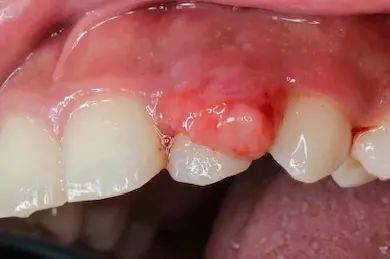

临床表现方面,结节性红斑主要表现为对称分布的皮下结节,通常位于胫前区,伴有疼痛和压痛,但一般不形成溃疡,且常伴有发热、关节痛等全身症状,但无特异性系统损害。结节多在数周内自行消退,可能复发。相比之下,白塞氏病的皮肤损害可类似结节性红斑,但常伴有其他典型特征:复发性口腔溃疡(至少每年发作3次)、生殖器溃疡、眼部病变(如葡萄膜炎)、关节炎,以及神经系统、胃肠道或血管受累的表现。白塞氏病的皮肤结节可能更易形成脓疱或溃疡,且病程慢性、反复发作。

在诊断标准上,结节性红斑主要依赖临床特征和活检(显示脂膜炎),需排除其他病因。而白塞氏病的诊断通常依据国际研究小组标准,包括复发性口腔溃疡加上至少两项其他表现(如生殖器溃疡、眼部病变、皮肤病变或针刺反应阳性)。其中,针刺反应(皮肤对轻微创伤的超敏反应)是白塞氏病的特征性表现,有助于鉴别。